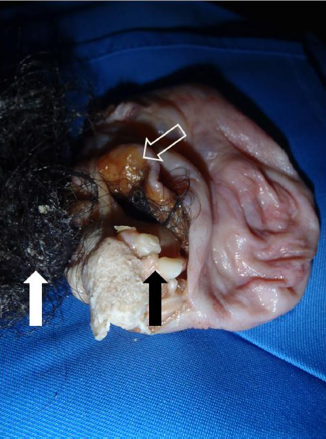

患者,35岁,女性。因下腹部疼痛伴呕吐和全身皮肤瘙痒一天就诊。院内检查显示下腹部局限性疼痛。全血细胞计数、血清淀粉酶正常。X线检查排除腹腔游离气体。腹部CT显示左卵巢囊肿,可见钙化灶。在全麻下腹腔镜检查发现一个附着于左侧卵巢的囊肿局部发生扭转,于是施行手术将囊肿去除。患者手术后恢复良好,术后第一天回家,没有出现全身皮肤瘙痒。术后对囊肿病检显示可见头发和牙齿,组织学分析显示为良性畸胎瘤。

数中切除的囊肿,其内容物包括牙齿(黑色实线箭头),头发(白色箭头)和皮脂(白色概述箭头)。